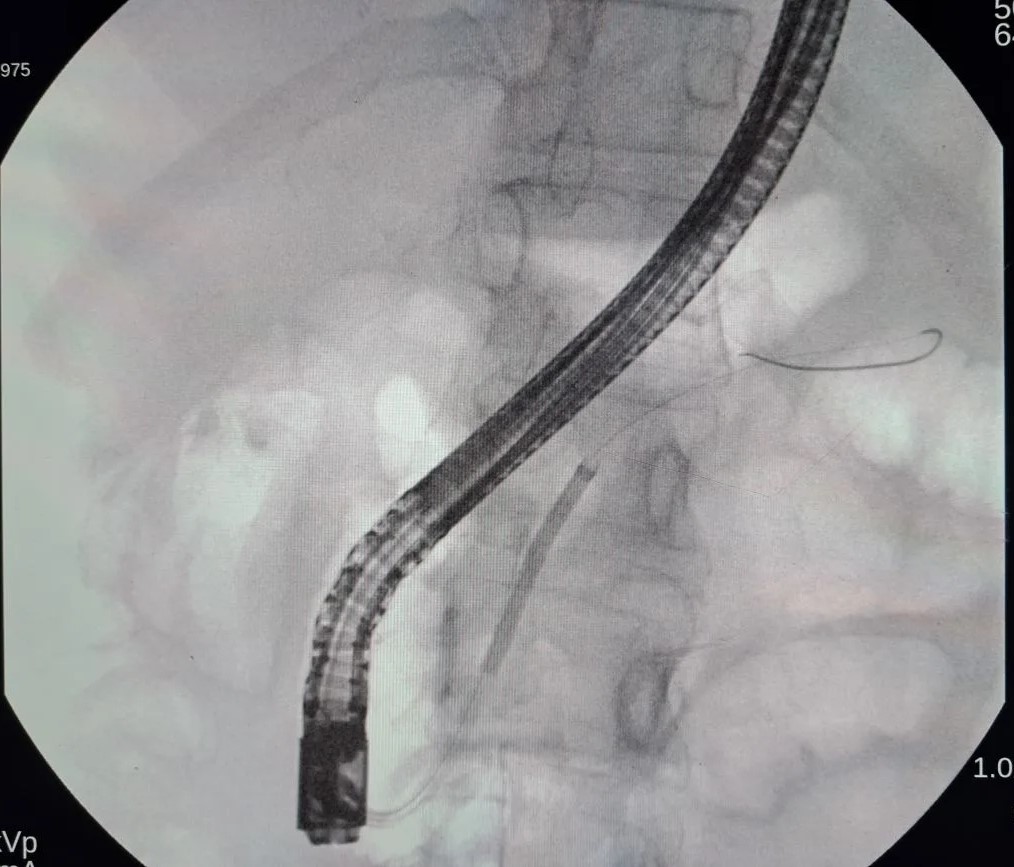

Контактная ударно-волновая литотрипсия представляет собой малоинвазивный метод дробления конкрементов в главном протоке поджелудочной железы.

Операция выполняется доступом из ротовой полости без разреза, сразу после осмотра желудка и двенадцатиперстной кишки, через естественное отверстие для оттока желчи и панкреатического сока. Ход вмешательства контролируется двумя видеокамерами, со стороны просвета желудочно-кишечного тракта и дополнительной миниатурной видеокамерой внутри просвета протоковой системы поджелудочной железы.

При этом электро-гидравлическое воздействие разрушает камни на более мелкие фрагменты, которые затем могут быть удалены специальными эндоскопическими инструментами.